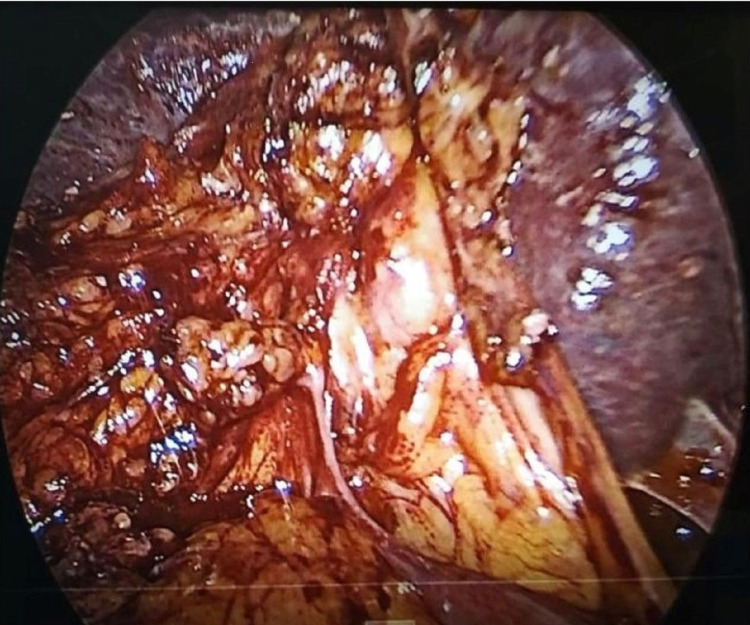

Pericholecystic adhesions (Figure 1), contracted gallbladder (Figure 2), gallbladder wall thickening, and frozen Calot’s triangle were observed significantly more among diabetic patients in comparison with nondiabetic patients. However, impaction of stone in Hartman’s pouch was present in six patients (8%) in the diabetic group in comparison with four patients (5.3%) in the nondiabetic group (Table 1).

Subtotal cholecystectomy was done in four patients (5.3%) in the diabetic group and two patients (2.6%) in the nondiabetic group. The reason for subtotal cholecystectomy was frozen Calot’s anatomy in both groups of patients. Conversion to open procedure was done in 4% of diabetic patients due to dense adhesions, altered anatomy, and inability to proceed to laparoscopy. The mean duration of surgery was taken as 90 minutes, and it exceeded in 52 diabetic patients (69.3%) and 27 nondiabetic patients (36%). A drain was given in 14 patients (18.6%) in the diabetic group and nine patients (12%) in the nondiabetic group. A tube drain was inserted in all patients with subtotal cholecystectomy and open conversion. Recovery from anesthesia was more than 20 minutes in 45 patients (60%) in the diabetic group and 18 patients (24%) in the nondiabetic, which was statistically significant. The reason for delayed anesthesia recovery was various intraoperative and metabolic factors in diabetes. Intraoperative injury was not reported in CBD or surrounding organs (Figure 3).